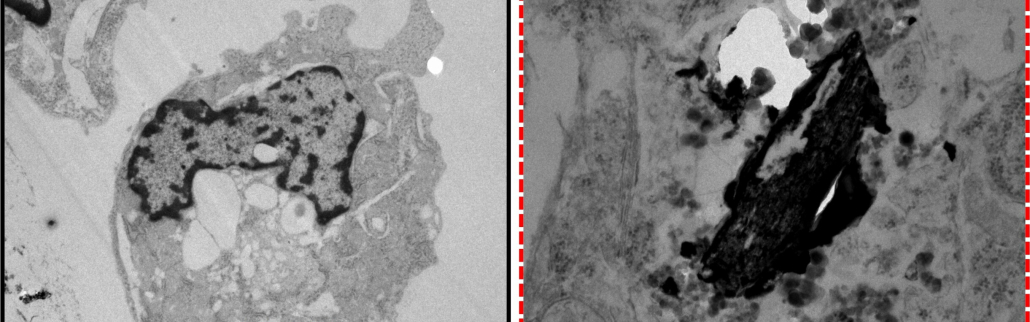

Investigación desarrollada en el Universidad de Murcia (UMU) recibió el premio “Joaquín Moreno Clavel”concedido por la Real Academia de Farmacia de la Región de Murcia en el ámbito de medio ambiente y salud, por su excepcional contribución al conocimiento de los efectos de la contaminación ambiental sobre las células cardíacas. La obra premiada, titulada «Análisis de los principales mecanismos proinflamatorios en patología cardiovascular mediante estimulación con lipopolisacáridos y partículas urbanas en cardiomiocitos auriculares de ratón»forma parte de la tesis doctoral de Darío Mandaglio ColladosEstudiante predoctoral del programa de Doctorado en Ciencias de la Salud de la Universidad de Murcia. Este estudio demuestra el potencial efecto inflamatorio que la contaminación ambiental y las partículas urbanas ejercen sobre los cardiomiocitos, las células responsables de la función contráctil del corazón. El Premio Joaquín Moreno Clavel se concedió conjuntamente con el trabajo de Miguel Motas, investigador de la UMU.

La investigación de Mandaglio aporta nueva evidencia sobre los mecanismos proinflamatorios implicados en la patología cardiovascular, fortaleciendo la relación entre la exposición a contaminantes ambientales y el desarrollo o empeoramiento de enfermedades del sistema cardiovascular, una de las principales causas de muerte en todo el mundo.